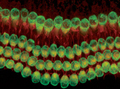

薬で聴覚の回復が可能に?

マウスを使った実験で,聴覚を担う有毛細胞の再生に成功した。難聴のうち最も一般的な感音難聴は,内耳にある有毛細胞が騒音,感染,薬剤などにより失われることが原因となる。哺乳類の有毛細胞は自然に再生しないため,治療によ…